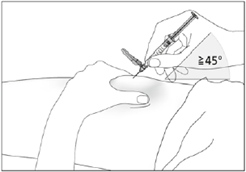

Wie gebe ich mir die Injektion?

1. Desinfizieren Sie Ihre Haut mit einem Alkoholtupfer und halten Sie die Haut zwischen Daumen und Zeigefinger fest, ohne Sie einzuklemmen (siehe Abbildung 9).

2. Führen Sie die Nadel so, wie es Ihnen Ihr Pflegepersonal oder Ihr Arzt resp. Ihre Ärztin gezeigt haben, vollständig in die Haut ein (siehe Abbildung 10).

3. Ziehen Sie vorsichtig am Kolben, um zu kontrollieren, dass Sie nicht in ein Blutgefäss gestochen haben. Wenn Sie Blut in der Spritze sehen, müssen Sie die Nadeln aus der Haut herausziehen und an einer anderen Stelle neu einstechen.

4. Injizieren Sie die Flüssigkeit langsam und gleichmässig. Halten Sie Ihre Haut die ganze Zeit zwischen Daumen und Zeigefinger fest.

5. Ziehen Sie nach dem Einspritzen der Flüssigkeit die Nadel heraus und lassen Sie Ihre Haut los.

6. Drücken Sie für einige Sekunden mit einem Stück Mullbinde oder einem sterilen Mulltupfer auf die Injektionsstelle.